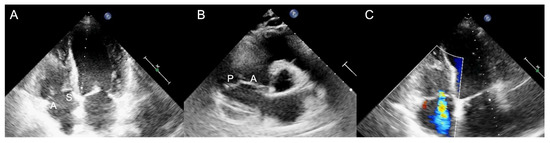

2.1. Two-Dimensional and Three-Dimensional Transthoracic and Transesophageal Echocardiography

3.1. Two-Dimensional and Three-Dimensional Transesophageal Echocardiography